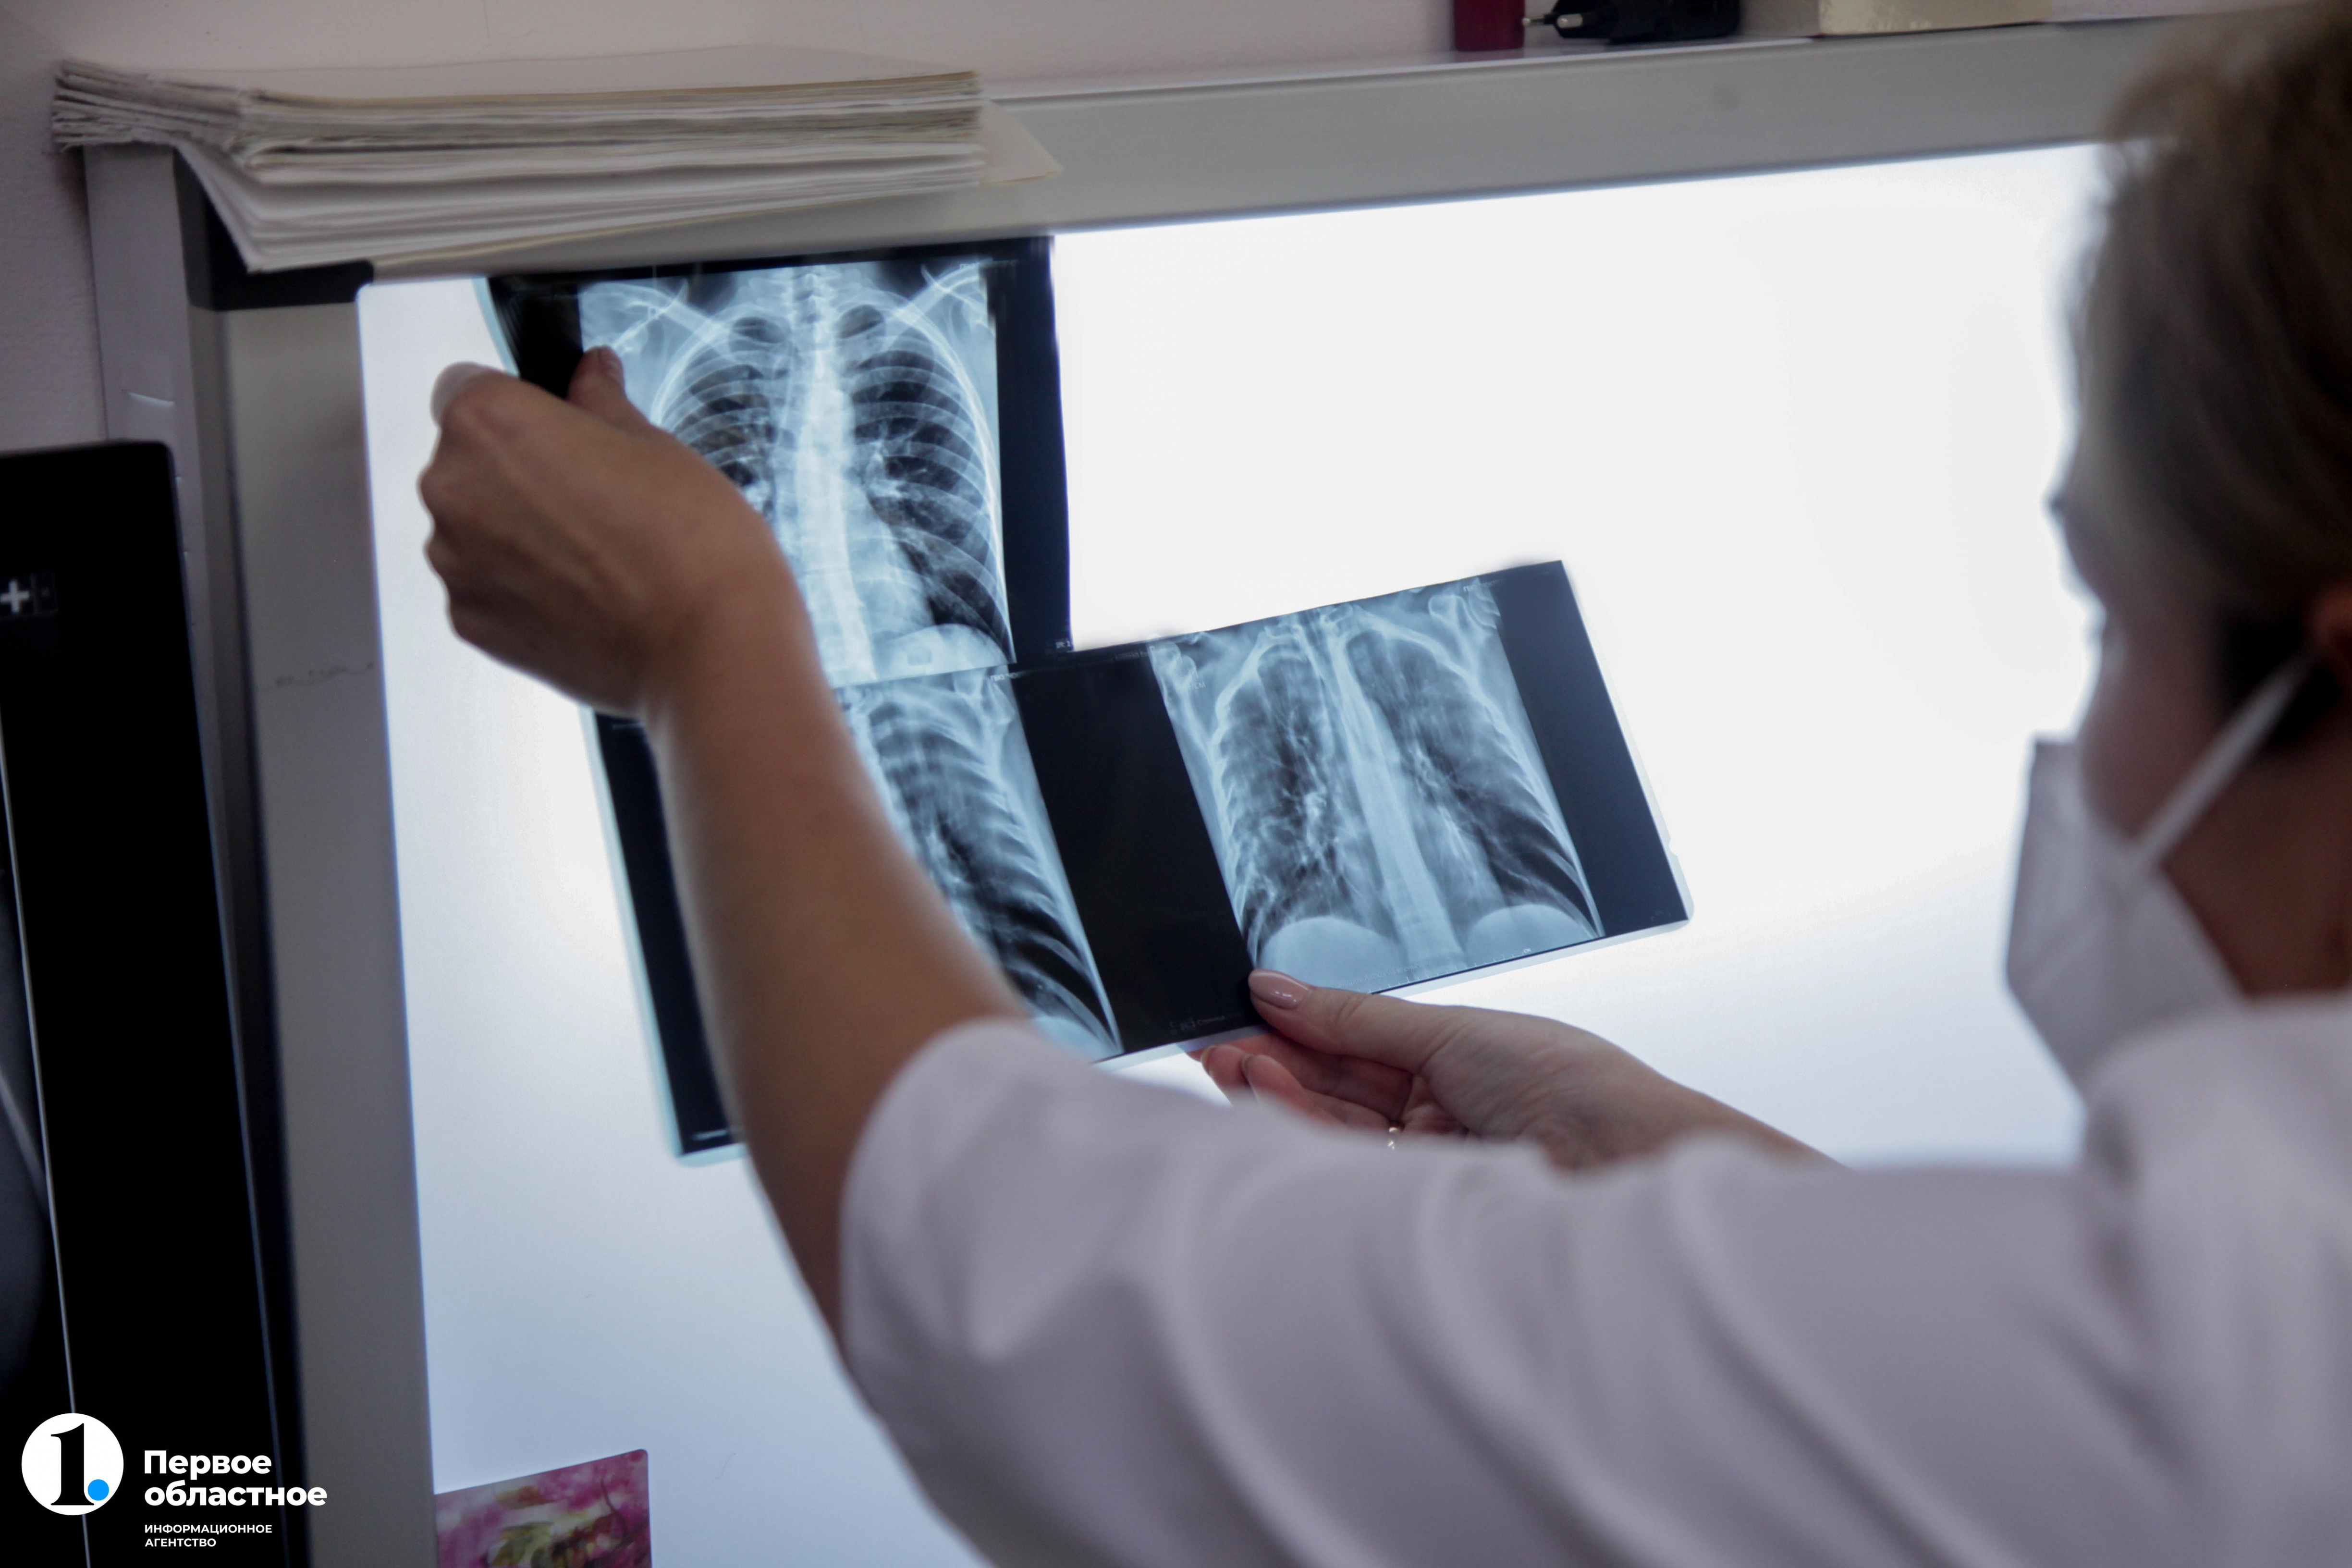

В Челябинской области с 1 августа начали проводить бесплатное углубленное обследование на туберкулез людей с ВИЧ-инфекцией. Помощь оказывается в рамках проекта «Зеленый коридор», выигравшего грант губернатора в размере 3 миллионов рублей. Обычная флюорография для диагностики заболевания у таких пациентов является неинформативной, поэтому им будут проводить обширный рентген грудной клетки и при необходимости отправлять на КТ. Об этом ИА «Первое областное» рассказали главный врач противотуберкулезного диспансера региона Марина Лехляйдер и руководитель общественной организации «Есть мнение» Юрий Авдеев.

Поэтому для вновь выявленных пациентов с ВИЧ-положительным статусом в Челябинской области в рамках проекта организовали незамедлительное обследование на туберкулез с помощью рентгенографии грудной клетки по системе «зеленый коридор». Для этого за человеком закрепляют специального куратора. Он буквально доводит человека до врача для незамедлительной диагностики, которая при необходимости будет включать в себя еще и компьютерную томографию.